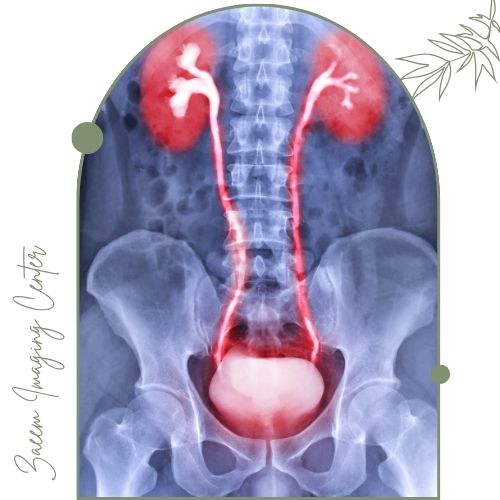

عکس رنگی مثانه (سیستوگرافی): تشخیص رفلاکس ادراری، تومور و عفونتهای مثانه را ممکن میسازد.

عکس رنگی مثانه و رتروگرید یورتروگرافی جهت بررسی مسیر و عملکرد مثانه و مجاری ادراری

سیستوگرافی روی بررسی ساختار و عملکرد مثانه تمرکز دارد و با تزریق ماده حاجب به مثانه انجام میشود. یورتروگرافی تصویربرداری تخصصی مجرای ادرار است. ماده حاجب از راه میزراه تزریق شده و برای تشخیص تنگی، آسیب یا انسداد میزراه کاربرد دارد. هر دو روش زیرمجموعه تصویربرداری رنگی هستند ولی ناحیه بررسی شده متفاوت است.